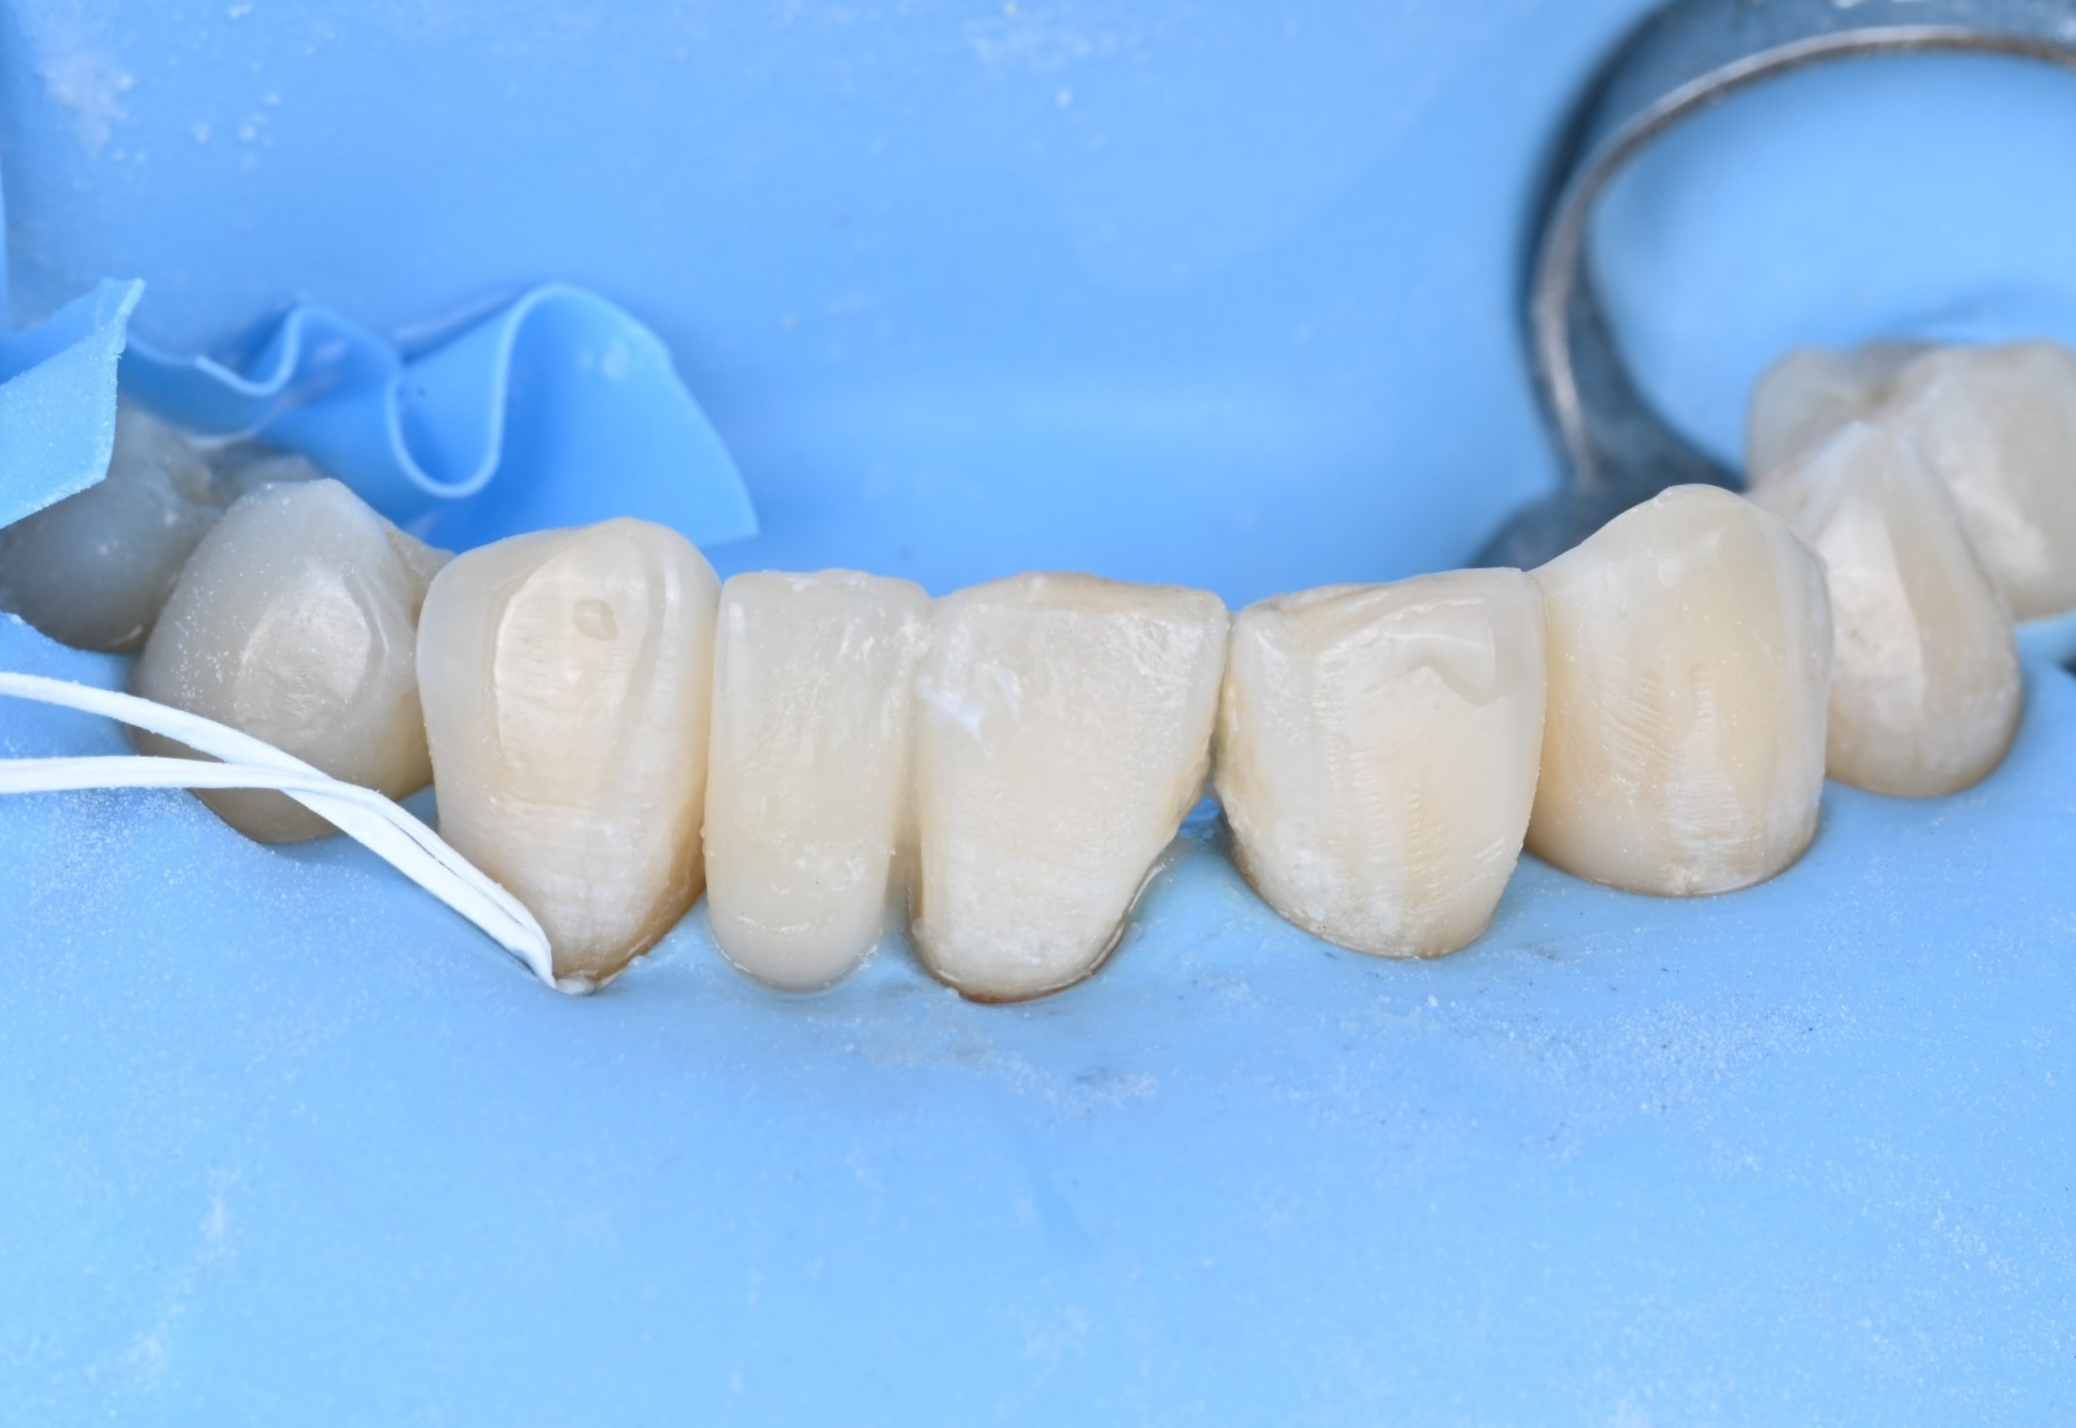

26.03.19 레진 치료를 위한 러버댐 장착

26.03.19 바이오클리어를 이용한 레진 수복

26.03.19